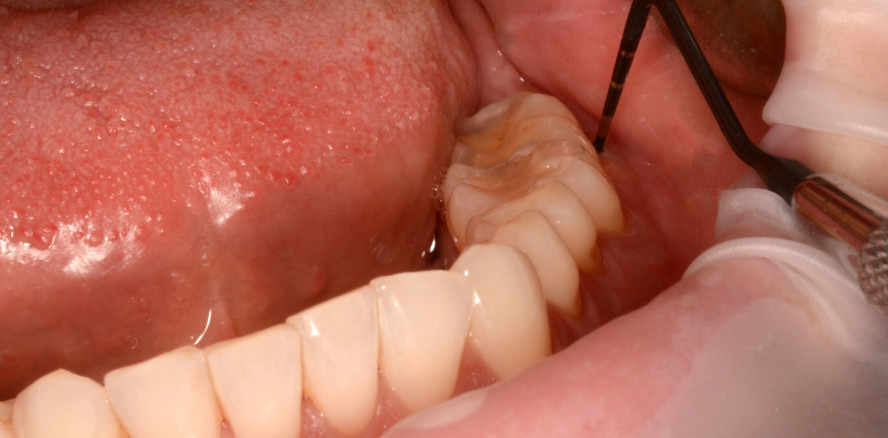

Eine gründliche subgingivale Instrumentierung stellt einen entscheidenden Schritt der Parodontitisbehandlung dar. Um eine effektive Entfernung von Biofilm und entzündlichem Granulationsgewebe zu gewährleisten, verwenden wir zum Scaling und zur Wurzelglättung bzw. zur minimalinvasiven Instrumentierung verschiedene Instrumente wie Gracey-­Küretten und Mini-Gracey-Küretten, Ultraschall- und Schallspitzen. Dennoch können Granulationsgewebe und Biofilmreste in tiefen Taschen und bei komplexer Wurzelanatomie verbleiben und so zu Rezidiven führen. Selbst durch mehrere subgingivale Instrumentierungen ist es oft nicht möglich, diese Taschen zu beseitigen.1, 2 Das einzige vorhersehbare Protokoll scheint ein chirurgisches Vorgehen mittels Lappenpräparation und Reinigung der Zahnoberfläche „unter Sicht“ zu sein.3 Dieser Eingriff ist allerdings auch kritisch zu bewerten, da er techniksensibel ist und von den Patienten zumeist nicht gewünscht wird.

Der Behandlungsplan wurde in drei Phasen durchgeführt. In den Pha­­sen I und II wurden die Anweisungen zur Mundhygiene verstärkt, um die Plaquekontrolle zu verbessern, gefolgt von einem supra- und subgingivalen Debridement mit Ultraschall (mectron GmbH) und Hand­instru­menten (Gracey-Küretten). Das Hypochlorit-Reinigungsgel (Perisolv) wurde adjuvant vor und während der Instrumentierung appliziert. Nach erfolgter Instrumentierung wurde vernetzte Hyaluronsäure (hyaDent BG) in die Taschen eingebracht, um die Wunde zu stabilisieren und die Regeneration zu fördern. Nach sieben Tagen wurde eine erneute Applika­tion der vernetzten Hyaluronsäure vorgenommen, um den natürlichen Abbau zu kompensieren, eine sekundäre bakterielle Rekolonisation zu verhindern und einen verlängerten regenerativen Effekt zu erzielen. Die Phase III (Erhaltungsphase) umfasste eine unterstützende Parodontitistherapie alle drei Monate mit Verbesserung der Mund­hygiene und stetiger Überwachung der Sondierungstiefe und des Sondierungsblutens.